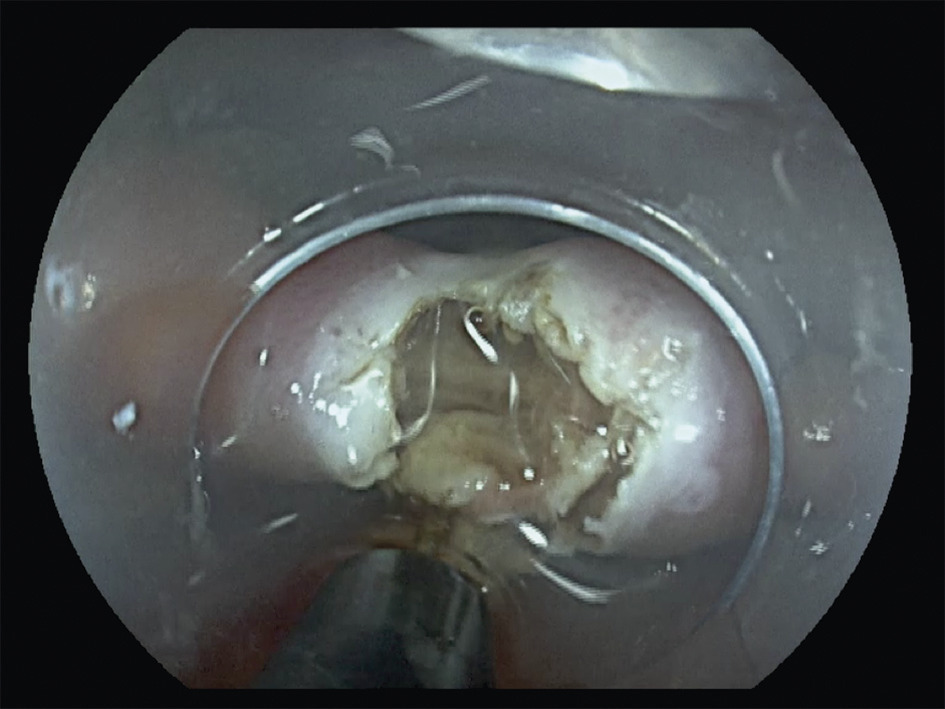

Le traitement endoscopique (fig. 2 à 5 ), ou myotomie transmuqueuse du cricopharyngien, peut être pratiqué par les ORL avec un diverticuloscope rigide ou par les gastro-entérologues experts, par endoscopie souple.2 Le diverticuloscope rigide impose une hyperextension cervicale parfois limitante. La diverticulotomie endoscopique consiste en une section de la paroi séparant le diverticule et l’œsophage, comprenant le muscle cricopharyngien, jusqu’à 5 mm du fond du diverticule. Elle offre des avantages par rapport à la chirurgie classique en termes de durée de procédure (< 1 heure) et d’hospitalisation. La réalimentation est plus précoce.

Taux médian de complication : 6 % par endoscopie souple. Ces techniques sont à préférer à la chirurgie chez les patients plus âgés et fragiles, malgré des récidives un peu plus nombreuses.